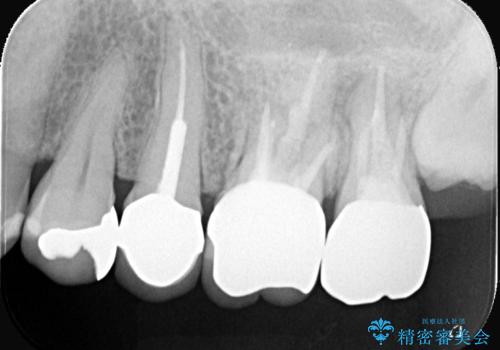

- 主訴:いつも物が詰まる場所があり気になる。衛生士に被せものと土台の境目に汚れが溜まっている箇所があると指摘され気になっている。

過去に入れた被せものと土台の歯との適合が悪く、隙間が出来ておりそこに汚れが溜まりやすい状態になっていました。セラミッククラウンでのやり替えとなりました。

唇側マージン不適なこと説明し、審美性・適合性に優れたセラミッククラウン(スタンダード)でのやり替えとなりました。